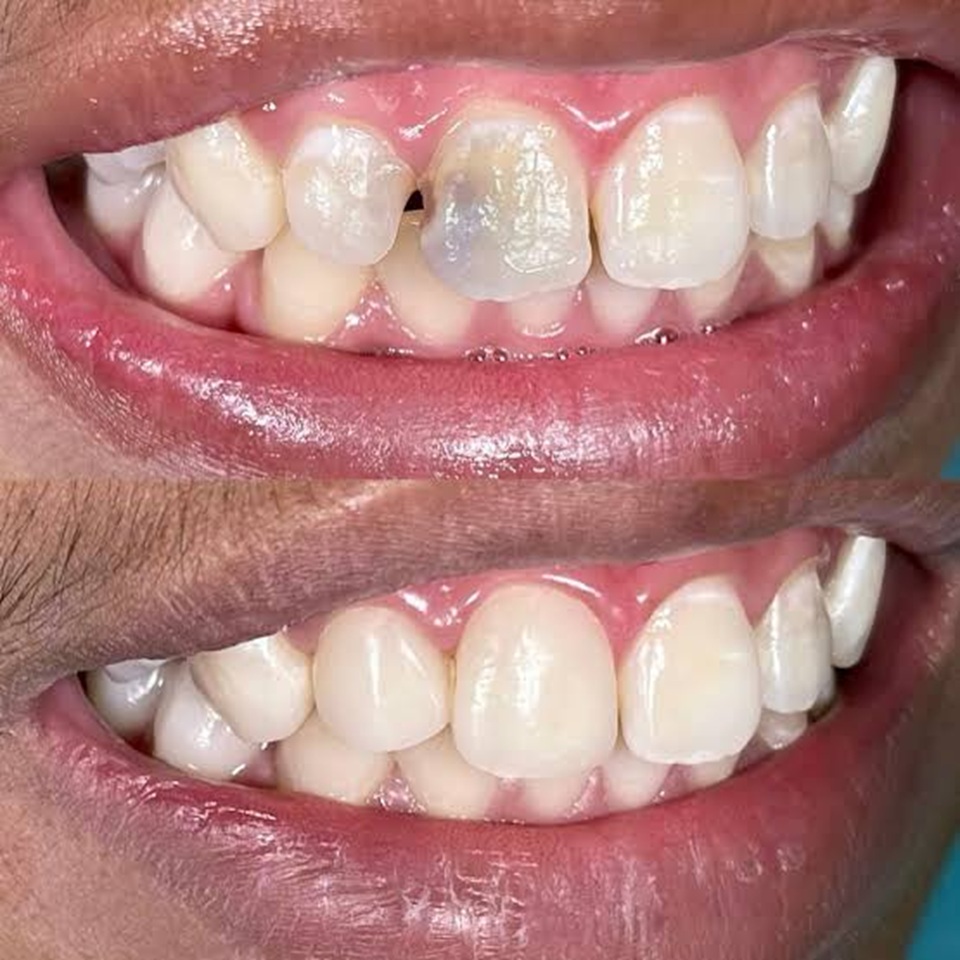

Endodontics is a specialized branch of dentistry focused on diagnosing and treating problems related to the tooth pulp and root canals. The most common procedure is root canal therapy, which removes infected or inflamed pulp to relieve pain, eliminate infection, and save the natural tooth. At our clinic, we use advanced and minimally invasive techniques to provide precise, comfortable, and effective treatments that protect your long-term oral health.

Endodontic care plays a vital role in saving teeth affected by deep decay, cracks, or injury. Using modern diagnostic tools, digital imaging, and magnification, we carefully clean and disinfect the canals, then seal them to prevent reinfection. These advanced methods ensure greater accuracy, less discomfort, and faster healing.